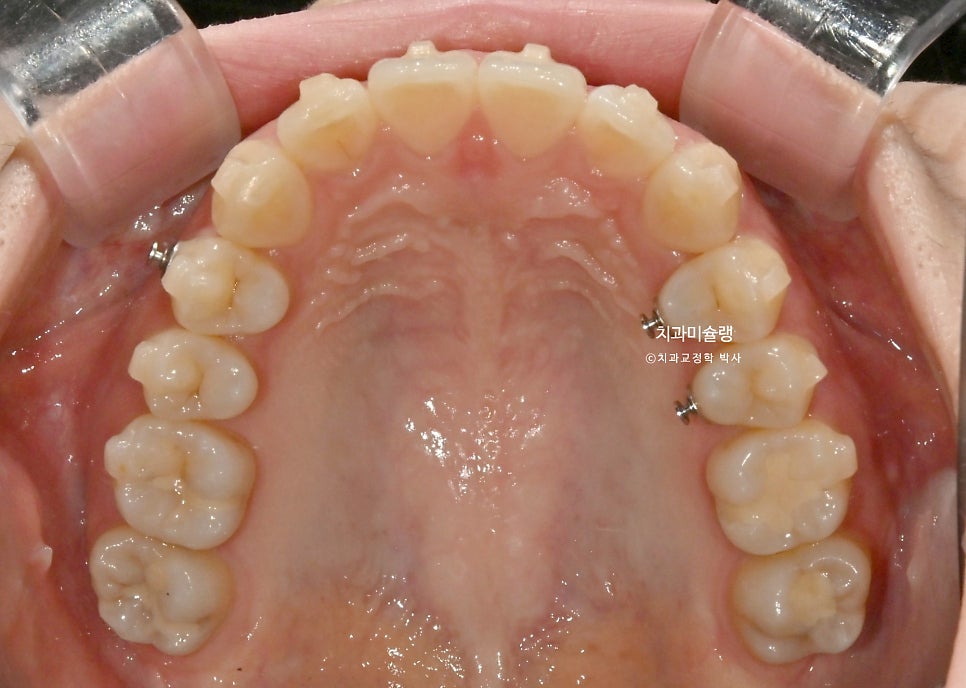

하악소구치 회전의 기술적 어려움

인비절라인 교정에서 투명장치만으로 가장 어려운 치아이동은 바로 <하악소구치의 회전> 입니다.

환자가 아무리 열심히 껴도 어태치먼트 한두개로는 택도 없는

치아이동이기에, 하악 소구치 회전이 요구되는 경우는 부가장치를 붙여서 해결해야 합니다.

여기 저기 붙어있는 금속 고리의 정체는 좀전에 언급한 작은어금니 회전을 위한 부가장치 입니다.

이 부가장치에 고무체인을 걸어놓음으로써 소구치의 회전이 첫세트에서 완료되었는데

4개월간의 회전 개선량을 표시해보면 이러합니다.